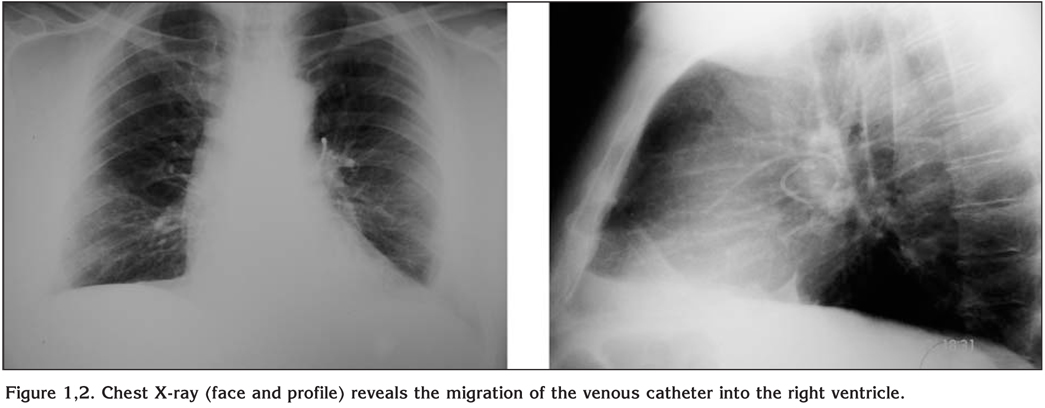

A 42-year-old woman with a history of breast cancer and hepatic metastatic disease underwent insertion of an implantable venous access catheter into the right subclavian vein (Seldinger technique). After eight months of treatment it was decided to remove the catheter due to reported possible thrombosis and obstruction. The patient was totally asymptomatic. A preoperative chest X-ray was consistent with migration of the catheter into the right ventricle (Figure 1,2). Percutaneous retrieval through right internal jugular vein and right femoral vein was unsuccessful as the catheter end was embedded in the myocardium. The catheter was removed via a median sternotomy through the main pulmonary artery without any further complications.

Figure 1,2